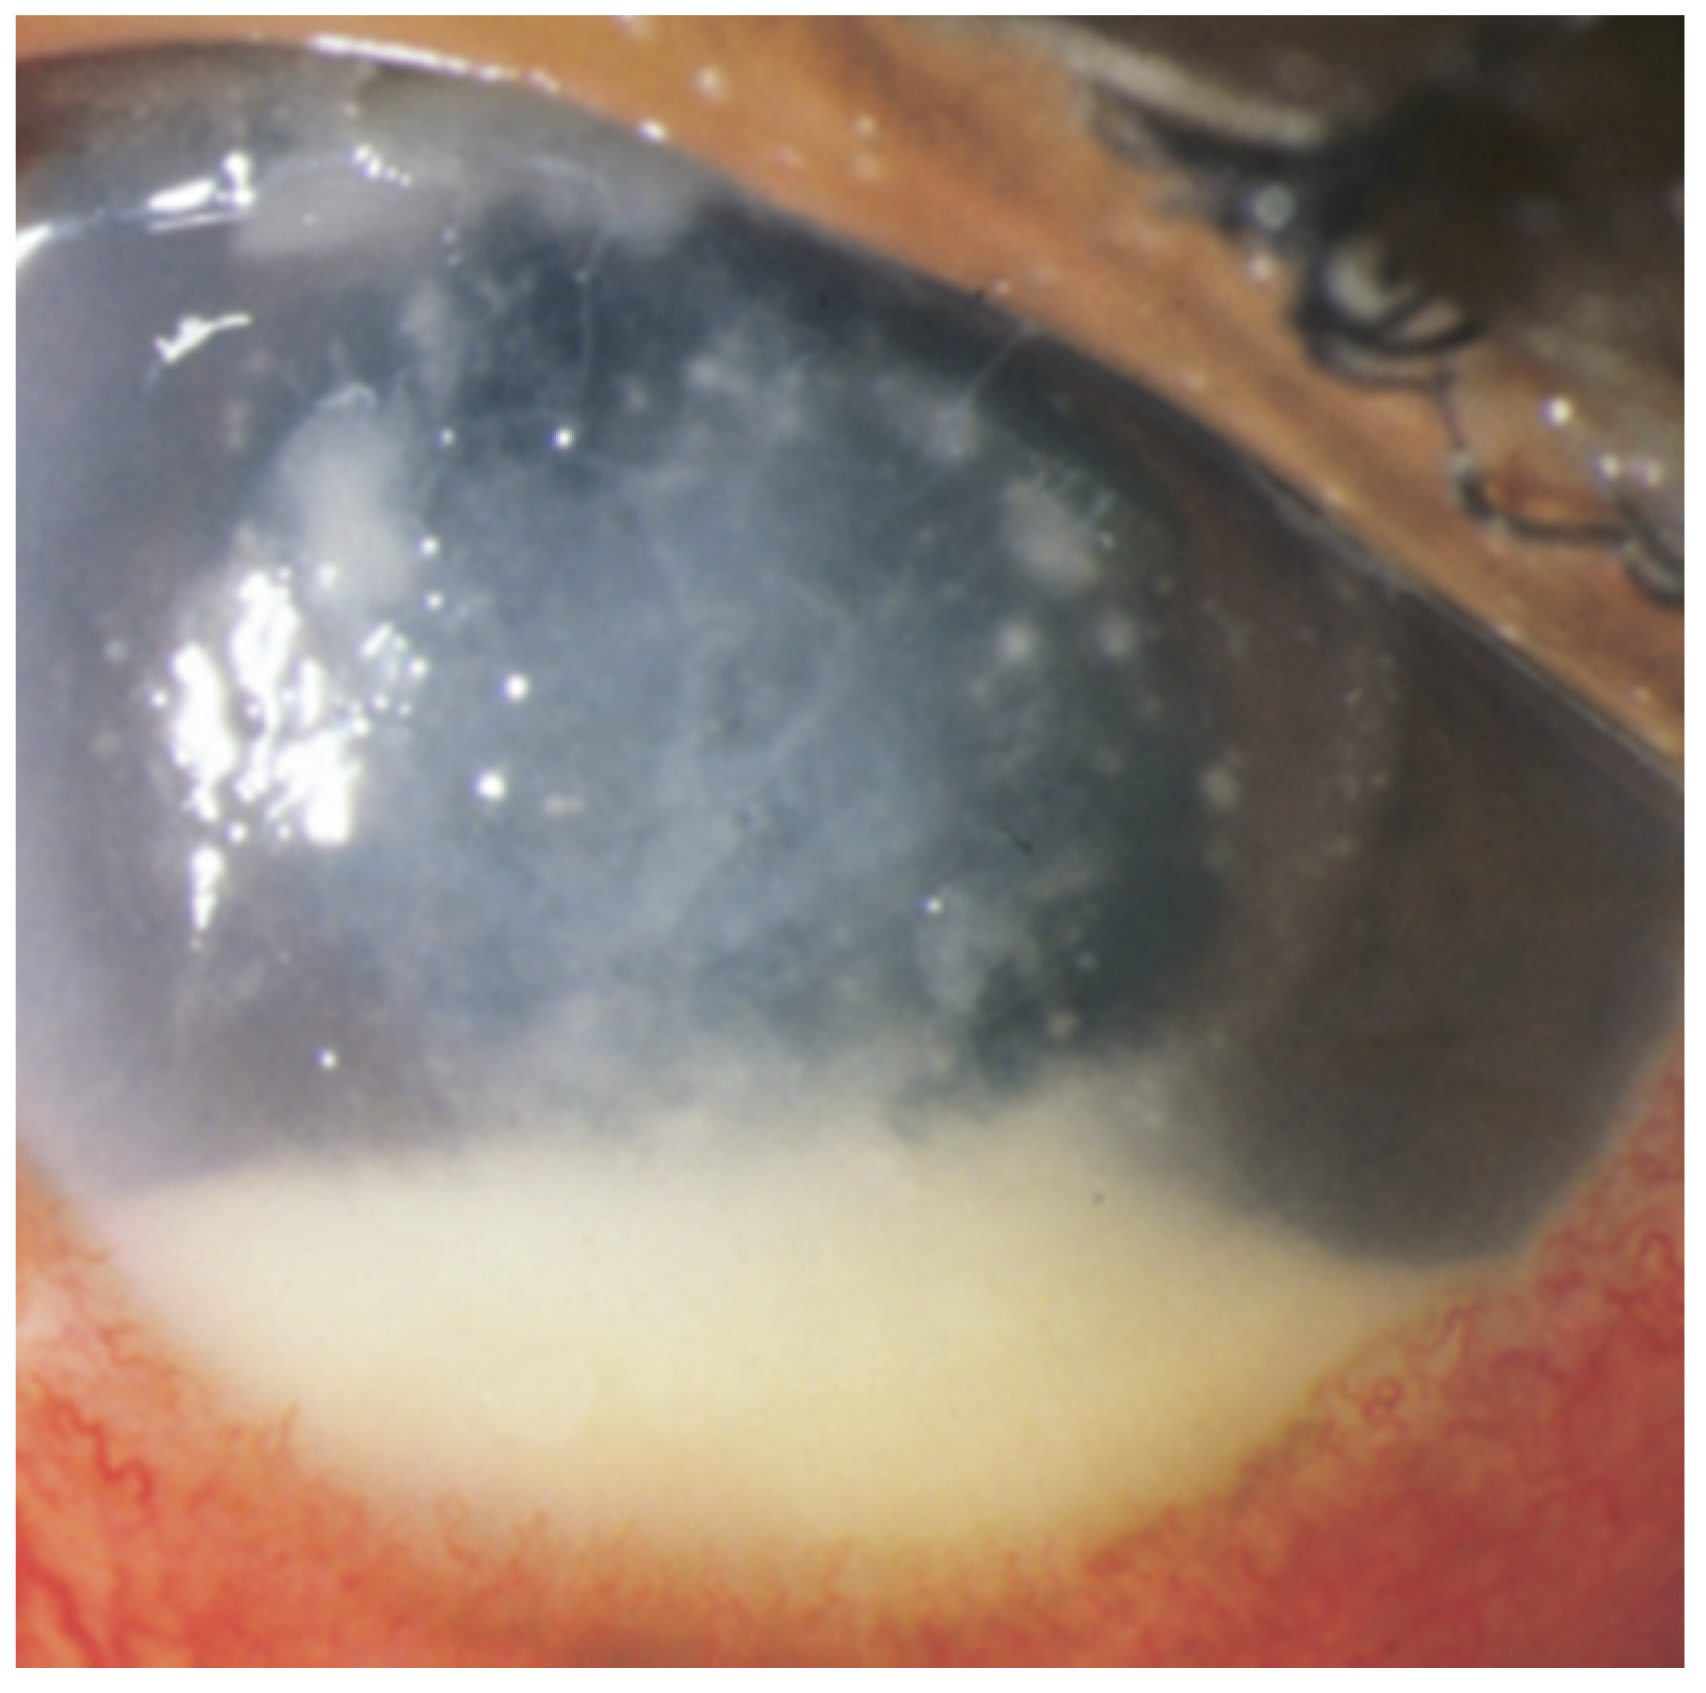

| Characteristic Lesions | Diffuse intraocular inflammation [1,2], subretinal abscess can also occue | Clumped appearance of intraocular inflammation [7], choroidal mass projecting into the vitreous chamber [4,7], chorioretinal creamy-white or “string of pearls” lesions (Candida species) [7,49] |